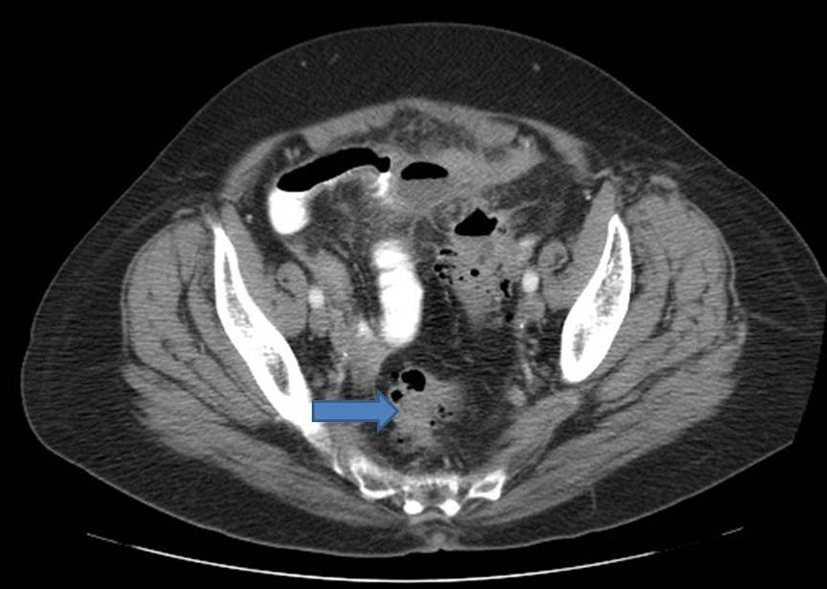

Patient was admitted for prolapsed hemorrhoids. Surgical consult was called and a CT scan of abdomen/pelvis was performed which showed colonic diverticulosis with no acute diverticulitis. The rectal mucosal appeared thickened compared with the remainder of the colon and it was advised that the possibility of a rectal or other colonic neoplasm be excluded (Fig. 1). Biopsy of the rectal mass was performed which showed malignant melanoma. Immunohistochemical stain performed showed the tumor cells to be positive for S-100, melan A and HMB-45 (Fig. 2-4) and negative for CD34, chromogranin, synaptophysin, CD20, AE1/3, CK20, CD3 and CK7. The patient was diagnosed as primary mucosal malignant melanoma. Whole body scan did not reveal any metastasis. Patient was referred to cancer center for further treatment.

![]() Click for large image | Figure 1. CT scan of abdomen showing thickening of the rectal mucosa. |